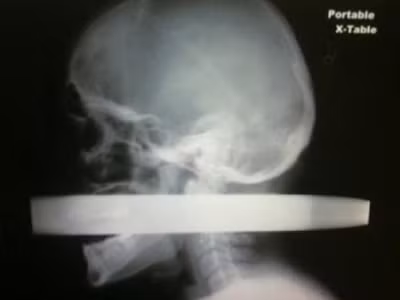

| Phim chụp của Andrew Driver Linn. |

Anh nói: "Tất cả những gì tôi nhớ là mình đi ngủ sau khi ăn tối và sau đó thức dậy trong bệnh viện. Sau khi nhìn thấy hình ảnh chụp lại thanh kim loại xuyên qua đầu và cổ mình, tôi cảm thấy thật mừng vì mình đã không nhớ gì cả”.